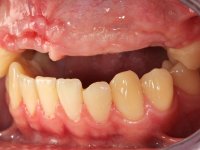

Paciente do sexo masculino, com 22 anos de idade e não fumador. Apresentou-se na consulta 6 meses após um acidente de viação em que perdeu os dentes 21, 22, 23 e 24. Os dentes 12 e 11 apresentavam mobilidade grau 3 apresentando-se também com extracção indicada. A arquitectura gengival da zona desdentada apresentava-se retraída e planificada.

O paciente foi observado conjuntamente e a dúvida que surgiu de imediato foi se seria possível com a regeneração óssea a efectuar poder ser reabilitada naturalmente a zona das papilas interdentárias. Nesse sentido foi feito um enceramento de diagnóstico que contemplaria as duas hipóteses, utilizando ou não a cerâmica gengival. A confecção desse enceramento foi fundamental para expor ao paciente a dificuldade da reabilitação. O wax-up deu origem a um mock-up que foi aprovado pelo paciente e que simultaneamente serviu de guia imagiológica. O caso foi planificado cirurgicamente e realizada uma guia cirúrgica com que foram colocados os implantes. Após 10 semanas foi feita a 1ª impressão para confecção da ponte provisória. Foram criados os primeiros perfis de emergência na gengiva artificial e foi digitalizado o modelo. Por processo de CAD-CAM foi confeccionada uma ponte provisória aparafusada baseada no enceramento de diagnóstico. A ponte trabalhou durante 8 semanas os tecidos moles que foram fielmente copiados numa impressão com técnica de moldeira aberta. Os transferes foram individualizados com resina composta para copiarem fielmente os perfis de emergência criados pela ponte provisória. Confeccionado o modelo de trabalho definitivo, foi realizada uma infra-estrutura em zircónio seguindo a orientação do enceramento de diagnóstico. O assentamento da infra-estrutura foi testado em boca e simultaneamente foi novamente impressionados os tecidos moles com um silicone fluido. Nessa consulta foi feito o levantamento da cor. Os dentes 13 e 23 apresentavam uma saturação anormalmente forte que resolvemos não valorizar, optando por privilegiar a relação com o sector antero-inferior. Foi realizada uma nova gengiva artificial com a impressão que acompanhou a impressão de arrasto com a infra-estrutura. Após a colocação da cerâmica na infra-estrutura foram coladas as meso-estruturas. O trabalho final foi aparafusado lentamente permitindo a adaptação dos tecidos moles.